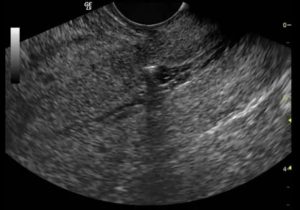

Диагностировать повреждения можно при помощи ультразвукового исследования, методом пальпации, на томографии разного вида. При этом каждый способ имеет свои плюсы. Так, во время УЗИ врач может оценить положение рубца, его размер и толщину.

- УЗИ. Исследование проводят для определения состояния матки во время беременности. УЗИ позволяет своевременно выявить маточные повреждения.

- УЗИ-исследования. При наступившей беременности это — единственно возможный вид исследования. Признаки, указывающие на неполноценность рубца — его неровность, прерывистость наружного контура, толщина рубца менее 3-3,5 мм.